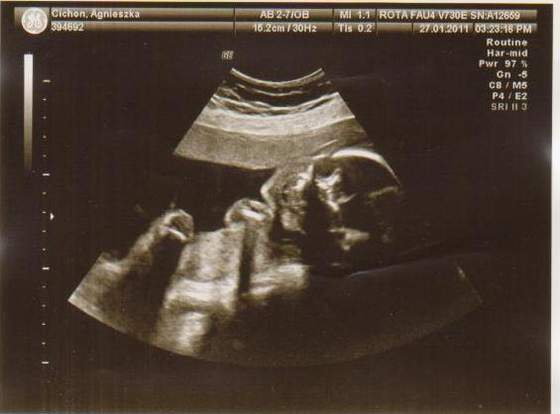

cześć dziewczyny to i ja chciałabym do Was dołączyć, właśnie znalazłam to forum. Mieszkam w Irlandii od 4 lat i mam synka 21 miesięcy, a teraz jestem w 28 tc bliźniaczej :-) dwie dziewczynki dwujajowe :-) też mnie trochę przeraża poród bliźniaków ale trzeba jakoś urodzić ;-) Pierwszy poród miałam jak marzenie szybko, sprawnie i nawet bez znieczulenia, mam nadzieję że i tym razem bęzie podobnie.

Hej podwojne mamunie:-)Ja juz rozpakowana dawno mamusia dubeltowka.Gratuluje wam serdecznie i witam w gronie tych wybranych hihiNiczego sie nie bojcie.Ciaxa blizniacza jest pod specjalna opieka.Czekaja was czeste wizyty w szpitalu i czeste ogladanie maluszkow na usg :-)